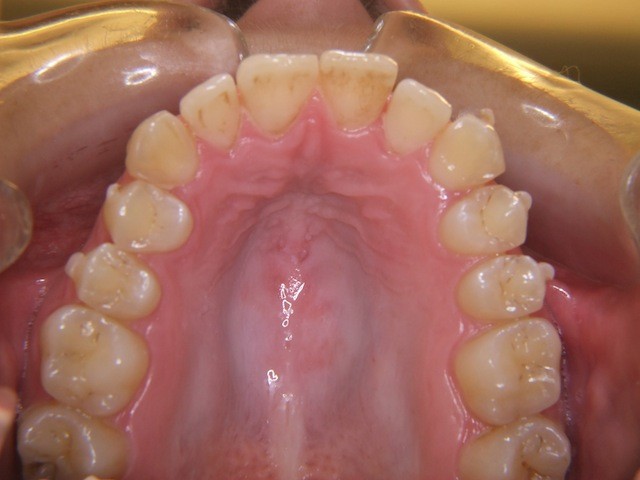

Vorher ----------------------------------- Nachher

Bilderserie Invisalignbehandlung Oberkiefer mit Stabilisierungsdraht am Schluss. Man beachte die Ansammlung von Belägen und Verfärbungen infolge Nischenbildung am Zahn der am meisten im Engstand steht.